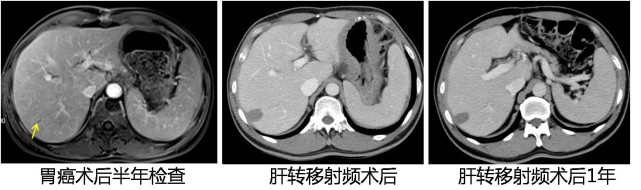

图片(胃癌患者术后复查的影像记录)

再看看这位远端胃癌患者,因为术后常规定期复查,在术后半年检查时发现在肝右叶有一个新发的很小的结节,我们就给他做了射频治疗,都不用手术,射频完了之后过了一年,这一片就坏死了,没什么活性了,现在三年多了患者活得非常好。所以早发现、早治疗很重要。

图片(患者术后复查的影像记录,肝上的大片阴影皆为转移灶)

相反的,像这两位患者,左图是乳腺癌患者的,术后一年半才复查;右图是结肠癌患者的,也是一年半以后复查,结果一看满肝都是转移,这个时候再治疗就比较困难了。当然我们也有各种药物,但是效果肯定没有及时发现的好。